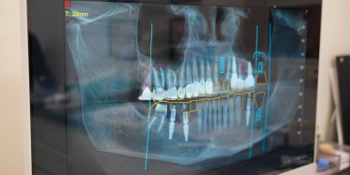

Встановлення зубного імпланта - це процедура, під час якої в кісткову тканину щелепи встановлюється штучний корінь зуба, зазвичай виготовлений із титану. Після приживлення на імплант встановлюється коронка, яка повністю відтворює функцію та зовнішній вигляд природного зуба. Такий метод вважається одним із найнадійніших способів відновлення втрачених зубів.

Процес імплантації складається з кількох етапів. Спочатку проводиться консультація, діагностика та планування лікування. Далі - хірургічне встановлення імпланта, після чого настає період остеоінтеграції, коли імплант зростається з кісткою. Завершальним етапом є встановлення коронки, яка забезпечує естетику та функціональність.

Важливо зазначити, що успіх імплантації залежить від професіоналізму лікаря та якості матеріалів. Перед процедурою обов’язково оцінюється стан кісткової тканини, загальне здоров’я пацієнта та можливі протипоказання. У деяких випадках може знадобитися додаткове нарощування кістки.